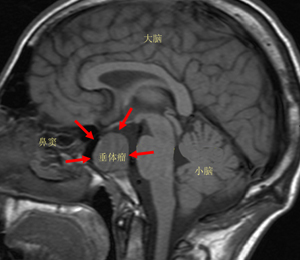

位于我們?nèi)梭w大腦的丘腦下部,有一卵圓形小體,醫(yī)學(xué)上稱之為垂體。垂體瘤是一組從垂體前葉和后葉及顱咽管上皮殘余細(xì)胞發(fā)生的腫瘤,是良性腺瘤。其主要表現(xiàn)為頭痛、視力障礙、內(nèi)分泌障礙,三者統(tǒng)稱垂體瘤三聯(lián)癥。

垂體僅占大腦體積的1/1000,看似微不足道,卻是人體神經(jīng)內(nèi)分泌的最高指揮中心,分泌5種主要神經(jīng)遞質(zhì)和激素,使全身內(nèi)分泌系統(tǒng)的激素保持在一個(gè)平衡狀態(tài)。一旦垂體分泌神經(jīng)遞質(zhì)的機(jī)能發(fā)生紊亂,整個(gè)內(nèi)分泌系統(tǒng)就會(huì)崩潰,過度分泌便形成了垂體瘤。